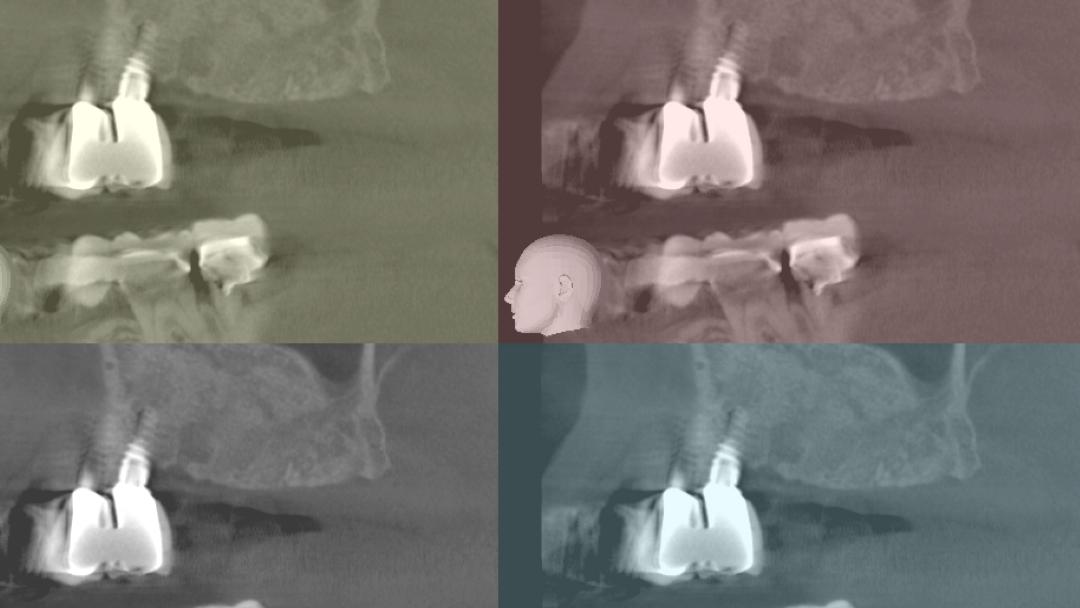

Ψηφιακή Εμφυτευματολογία (Μέρος 1 – ΧΕΙΡΟΥΡΓΙΚΗ) Ασφάλεια & Προβλεψιμότητα στην Εμφυτευματολογία

Conduct date:

21-22/04/2018 09-10/06/2018